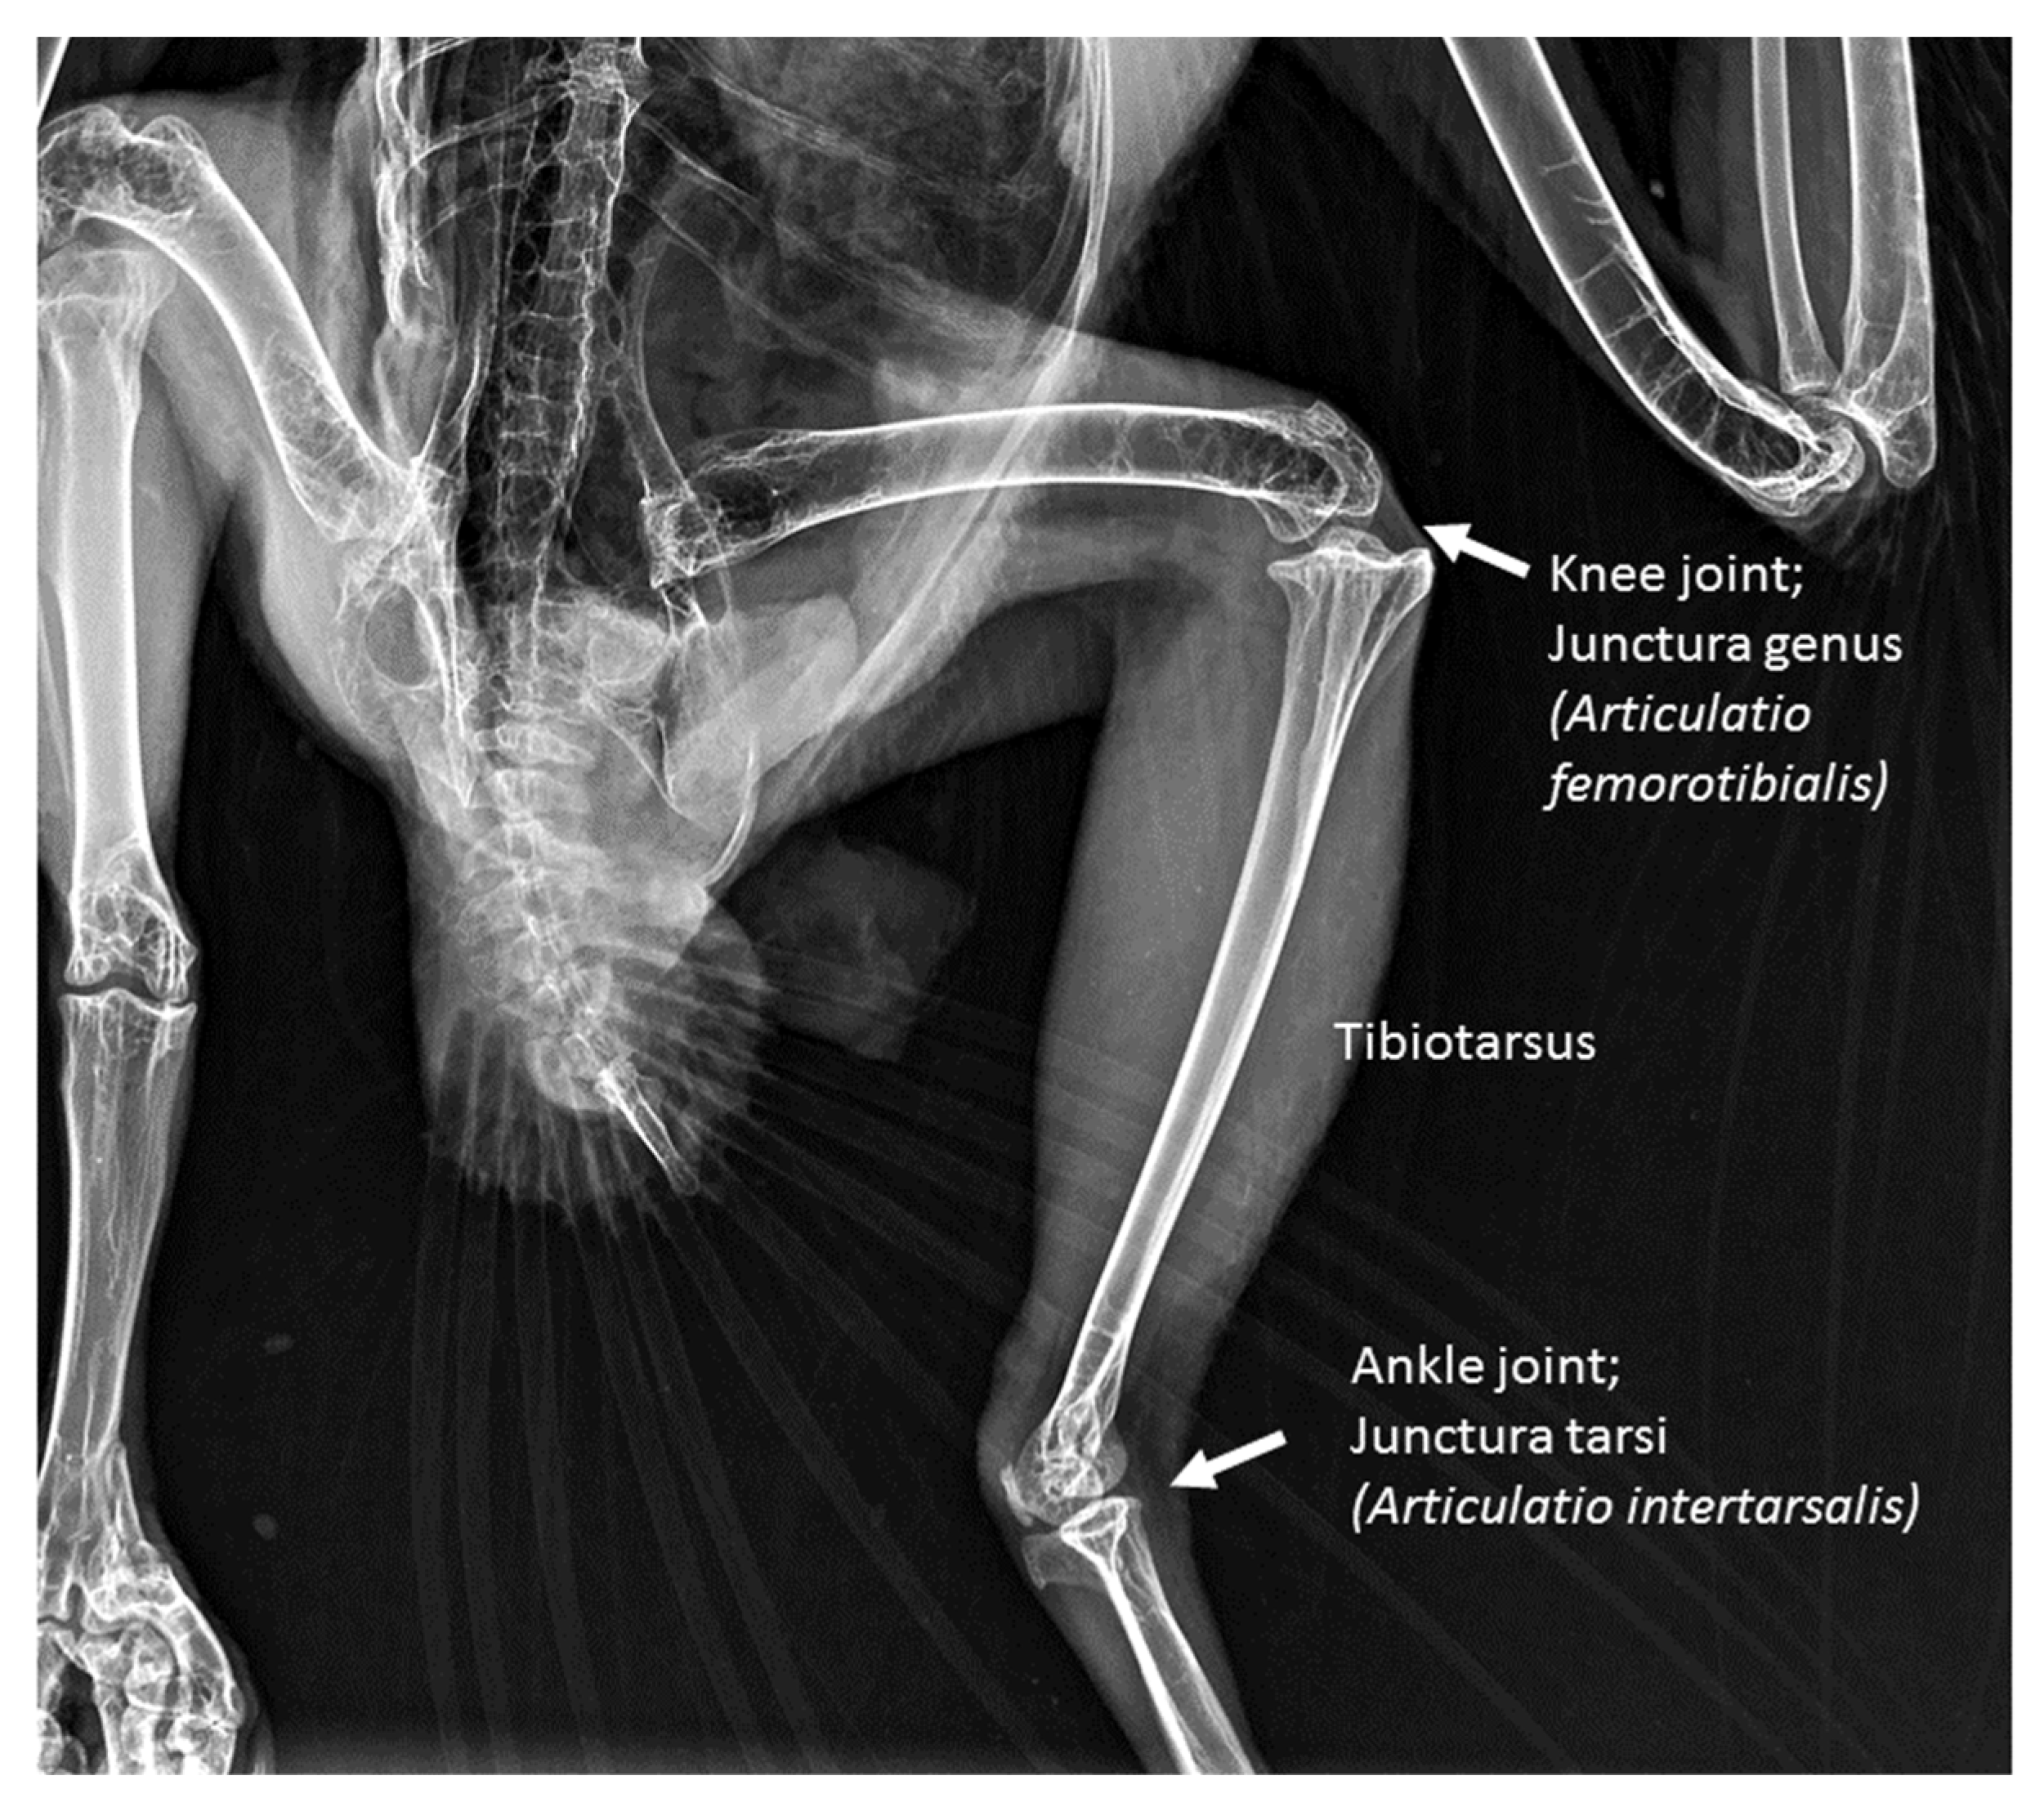

2.1. Sample Collection and Preparation